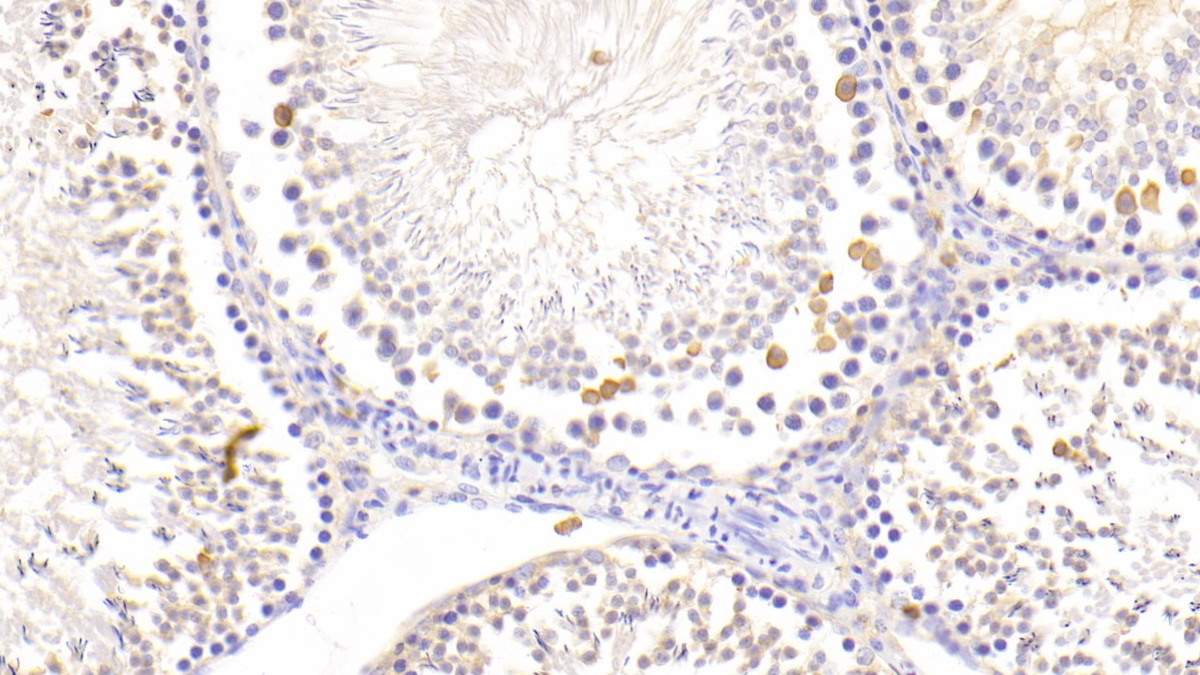

DAB staining on IHC-P; Samples: Rat Testis Tissue; Primary Ab: 20μg/ml Rabbit Anti-Rat LZM Antibody Second Ab: 2μg/mL HRP-Linked Caprine Anti-Rabbit IgG Polyclonal Antibody (Catalog: SAA544Rb19)